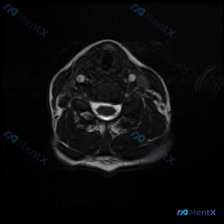

今天碰到一个有意思的情况:临床提示椎间盘病变,只给了一张颈部MRI T2序列轴位图像,咱们一起来理理思路。 病例基本信息 这是一张颈椎下段(推测C5-C6或C6-C7椎间盘水平)的T2轴位MRI,我们先读片: 1. 脊髓:信号均匀,没有明显异常高信号水肿或低信号出血,形态正常 2. 脑脊液:T2高信...

刚整理了一份很有临床意义的读片病例,怀疑椎间盘病变但单幅影像没有明显异常,把我的分析思路分享给大家。 病例影像基本信息 这是一份颈部MRI轴位T2加权像,扫描层面大致位于颈椎下段C5-C6或C6-C7椎间盘层面,图像质量清晰,没有明显伪影。 影像具体观察结果 1. 椎体:椎体后缘轮廓规整,骨髓信号均...

看到一个有意思的读片病例,整理了完整的分析思路分享给大家。 病例基本信息 核心问题:临床怀疑颈椎间盘病变,提供单张颈部MRI T2加权轴位影像,请判断病变情况。 影像学观察结果 这张图像是颈椎中下段水平的标准T2加权轴位影像,对比度良好无明显运动伪影,影像观察结果如下: 1. 椎间盘与骨性结构: 椎...